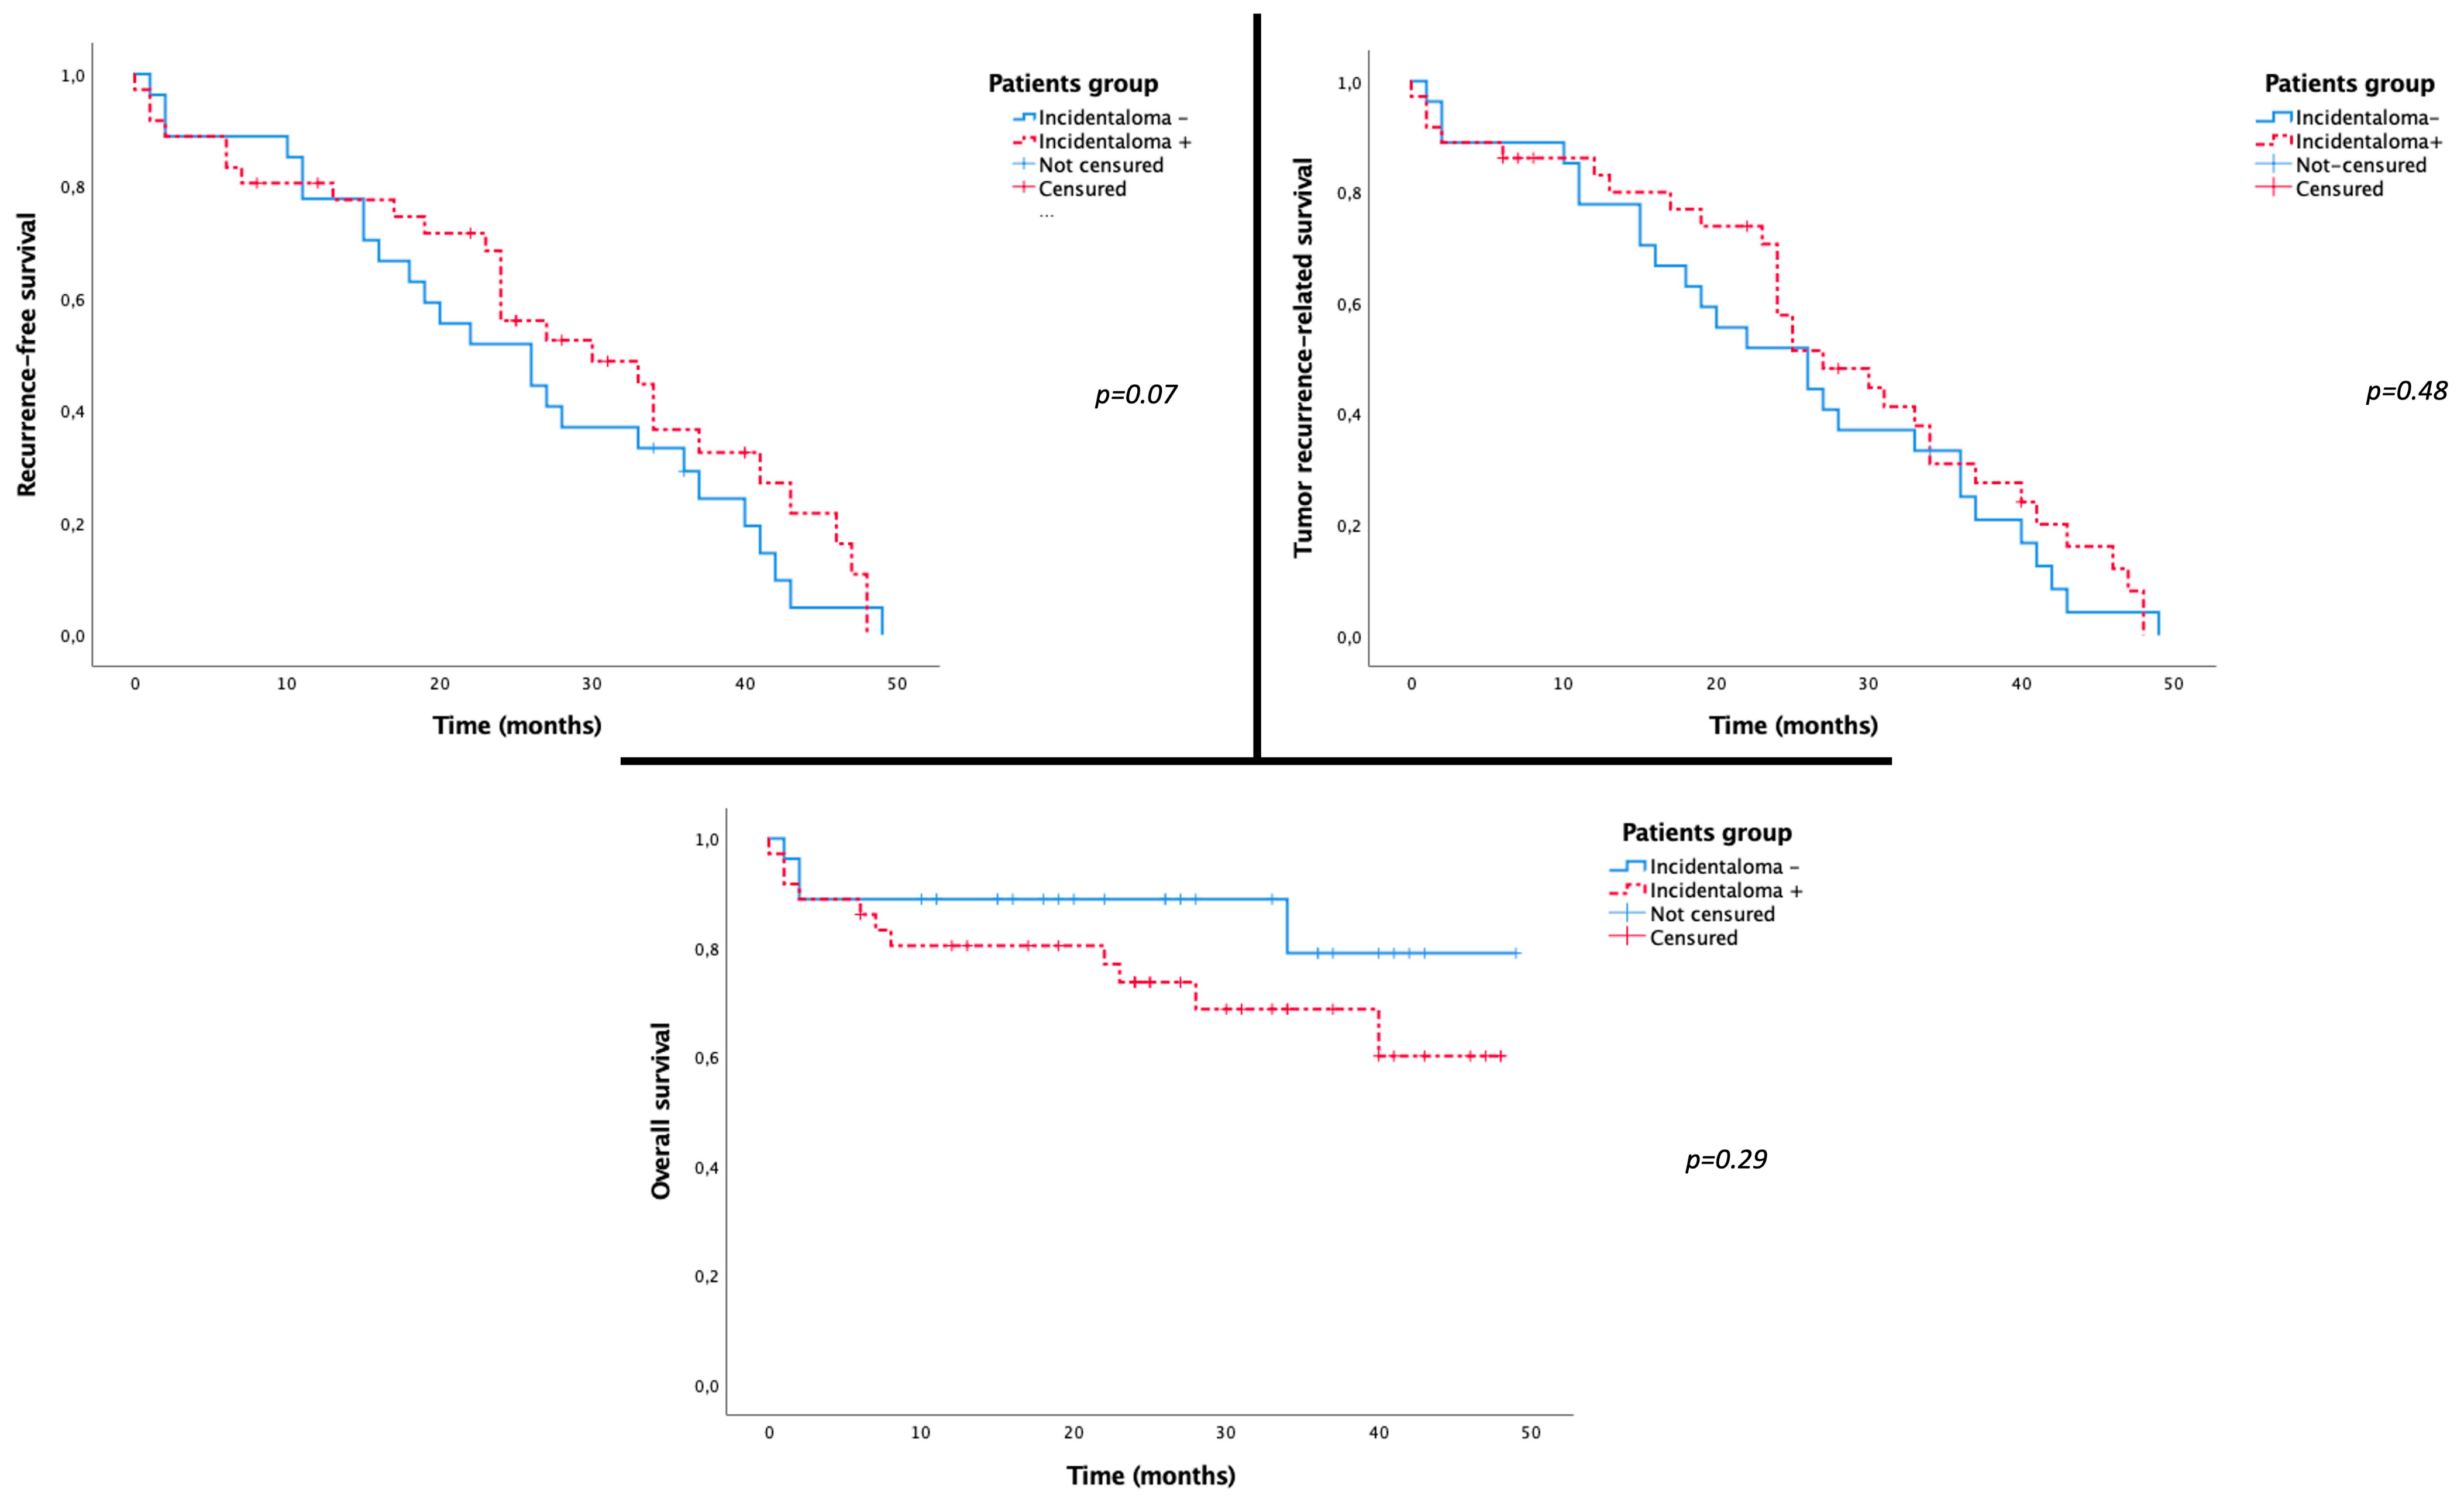

3.4. Correlation with Patient Prognosis